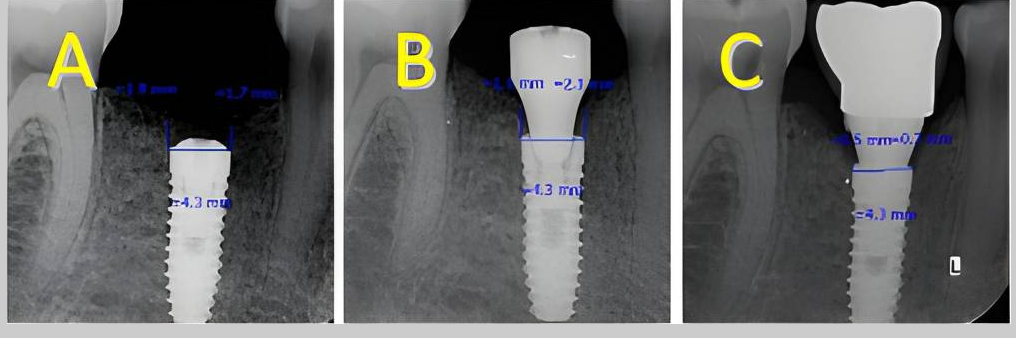

Measurements for the calculation of the MBL performed: A Preoperative evaluation; B immediate postoperative period; C 2 months after placement of the implants; D 36 month follow-up

A BL example in IDI #33 (A1: March 2019- A2: September 2023); B BR example in IDI #26 (B1: November 2019- B2: January 2020); C BO example in IDI #46 (C1: January 2019-C2 January 2020)